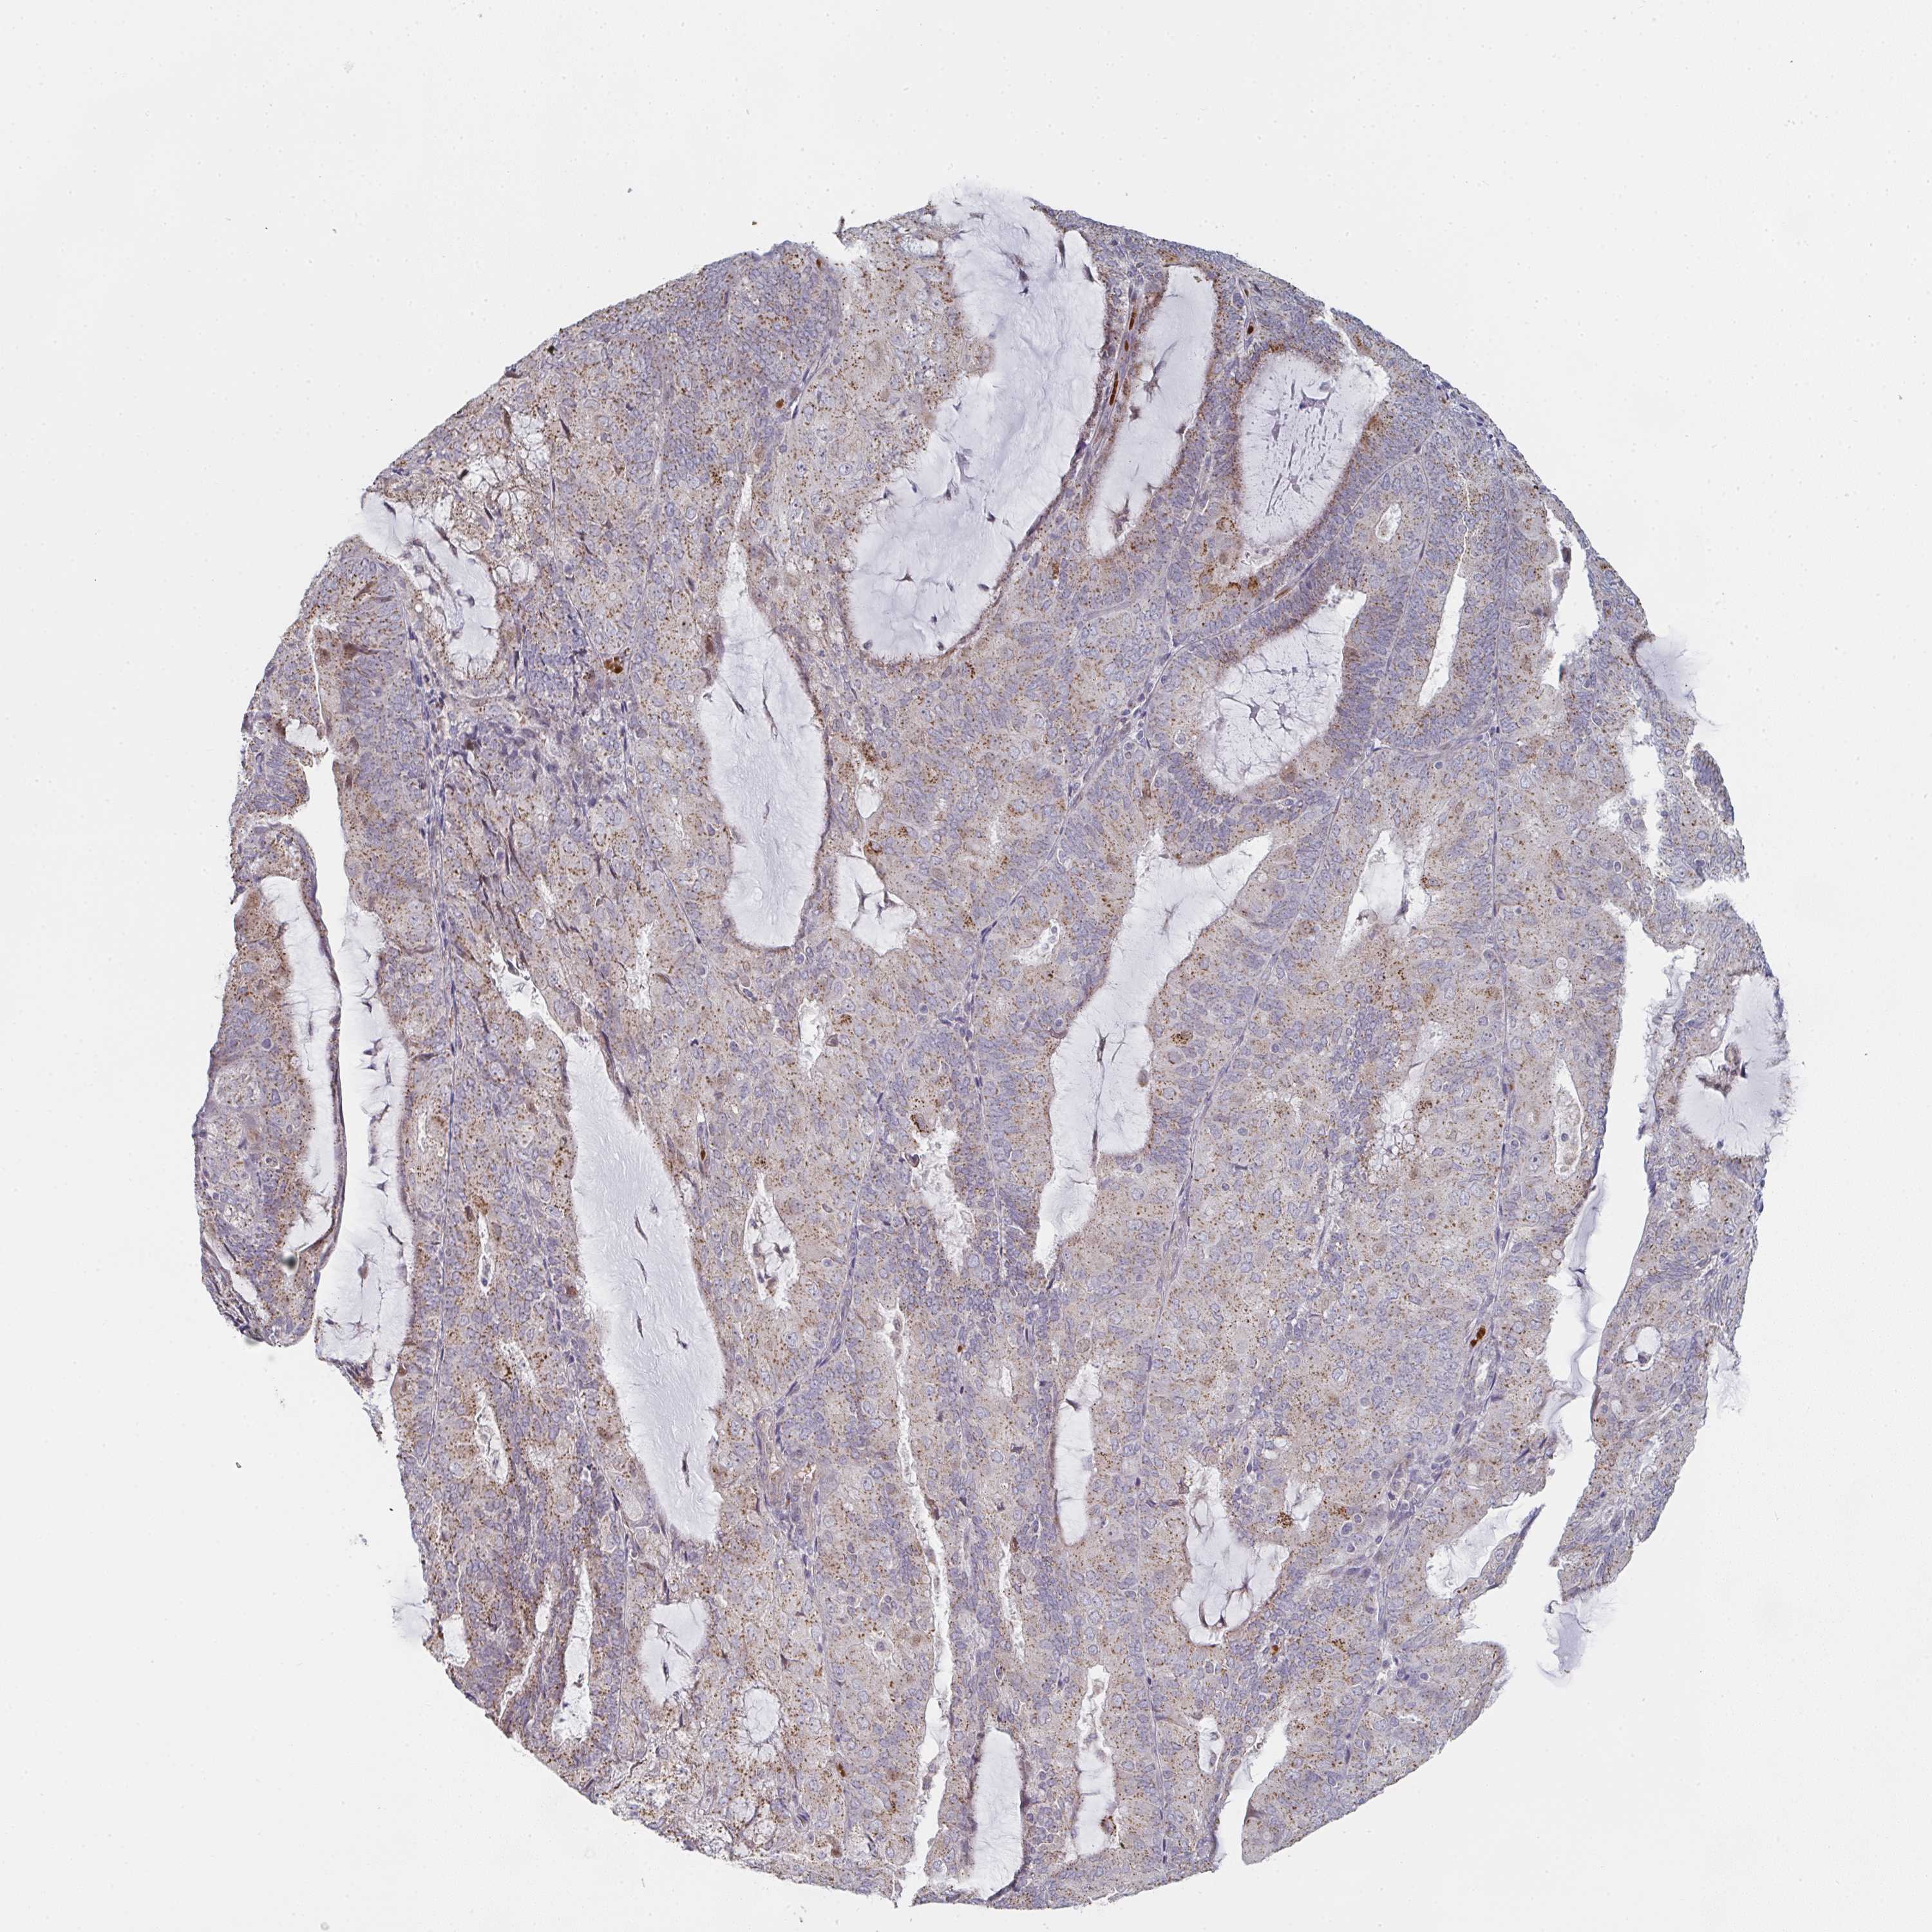

ENDOMETRIAL CANCER - Protein expressioni

A mouse-over function shows sample information and annotation data. Click on an image to view it in a full screen mode. Samples can be filtered based on level of antibody staining by selecting one or several of the following categories: high, medium, low and not detected. The assay and annotation is described here.

Note that samples used for immunohistochemistry by the Human Protein Atlas do not correspond to samples in the TCGA dataset.

Antibody stainingi

Antibody staining in the annotated cell types in the current human tissue is reported as not detected, low, medium, or high, based on conventional immunohistochemistry profiling in selected tissues. This score is based on the combination of the staining intensity and fraction of stained cells.

Each image is clickable and will lead to virtual microscopy that enables deeper exploration of all samples and also displays staining intensity scores, fraction scores and subcellular localization as well as patient and tissue information for each sample.

Antibody HPA023070

Antibody HPA056609

Staining

High

Medium

Low

Not detected

Intensity

Strong

Moderate

Weak

Negative

Quantity

>75%

75%-25%

<25%

None

Location

Nuclear

Cytoplasmic/membranous

Cytoplasmic/membranous,nuclear

Adenocarcinoma, NOS